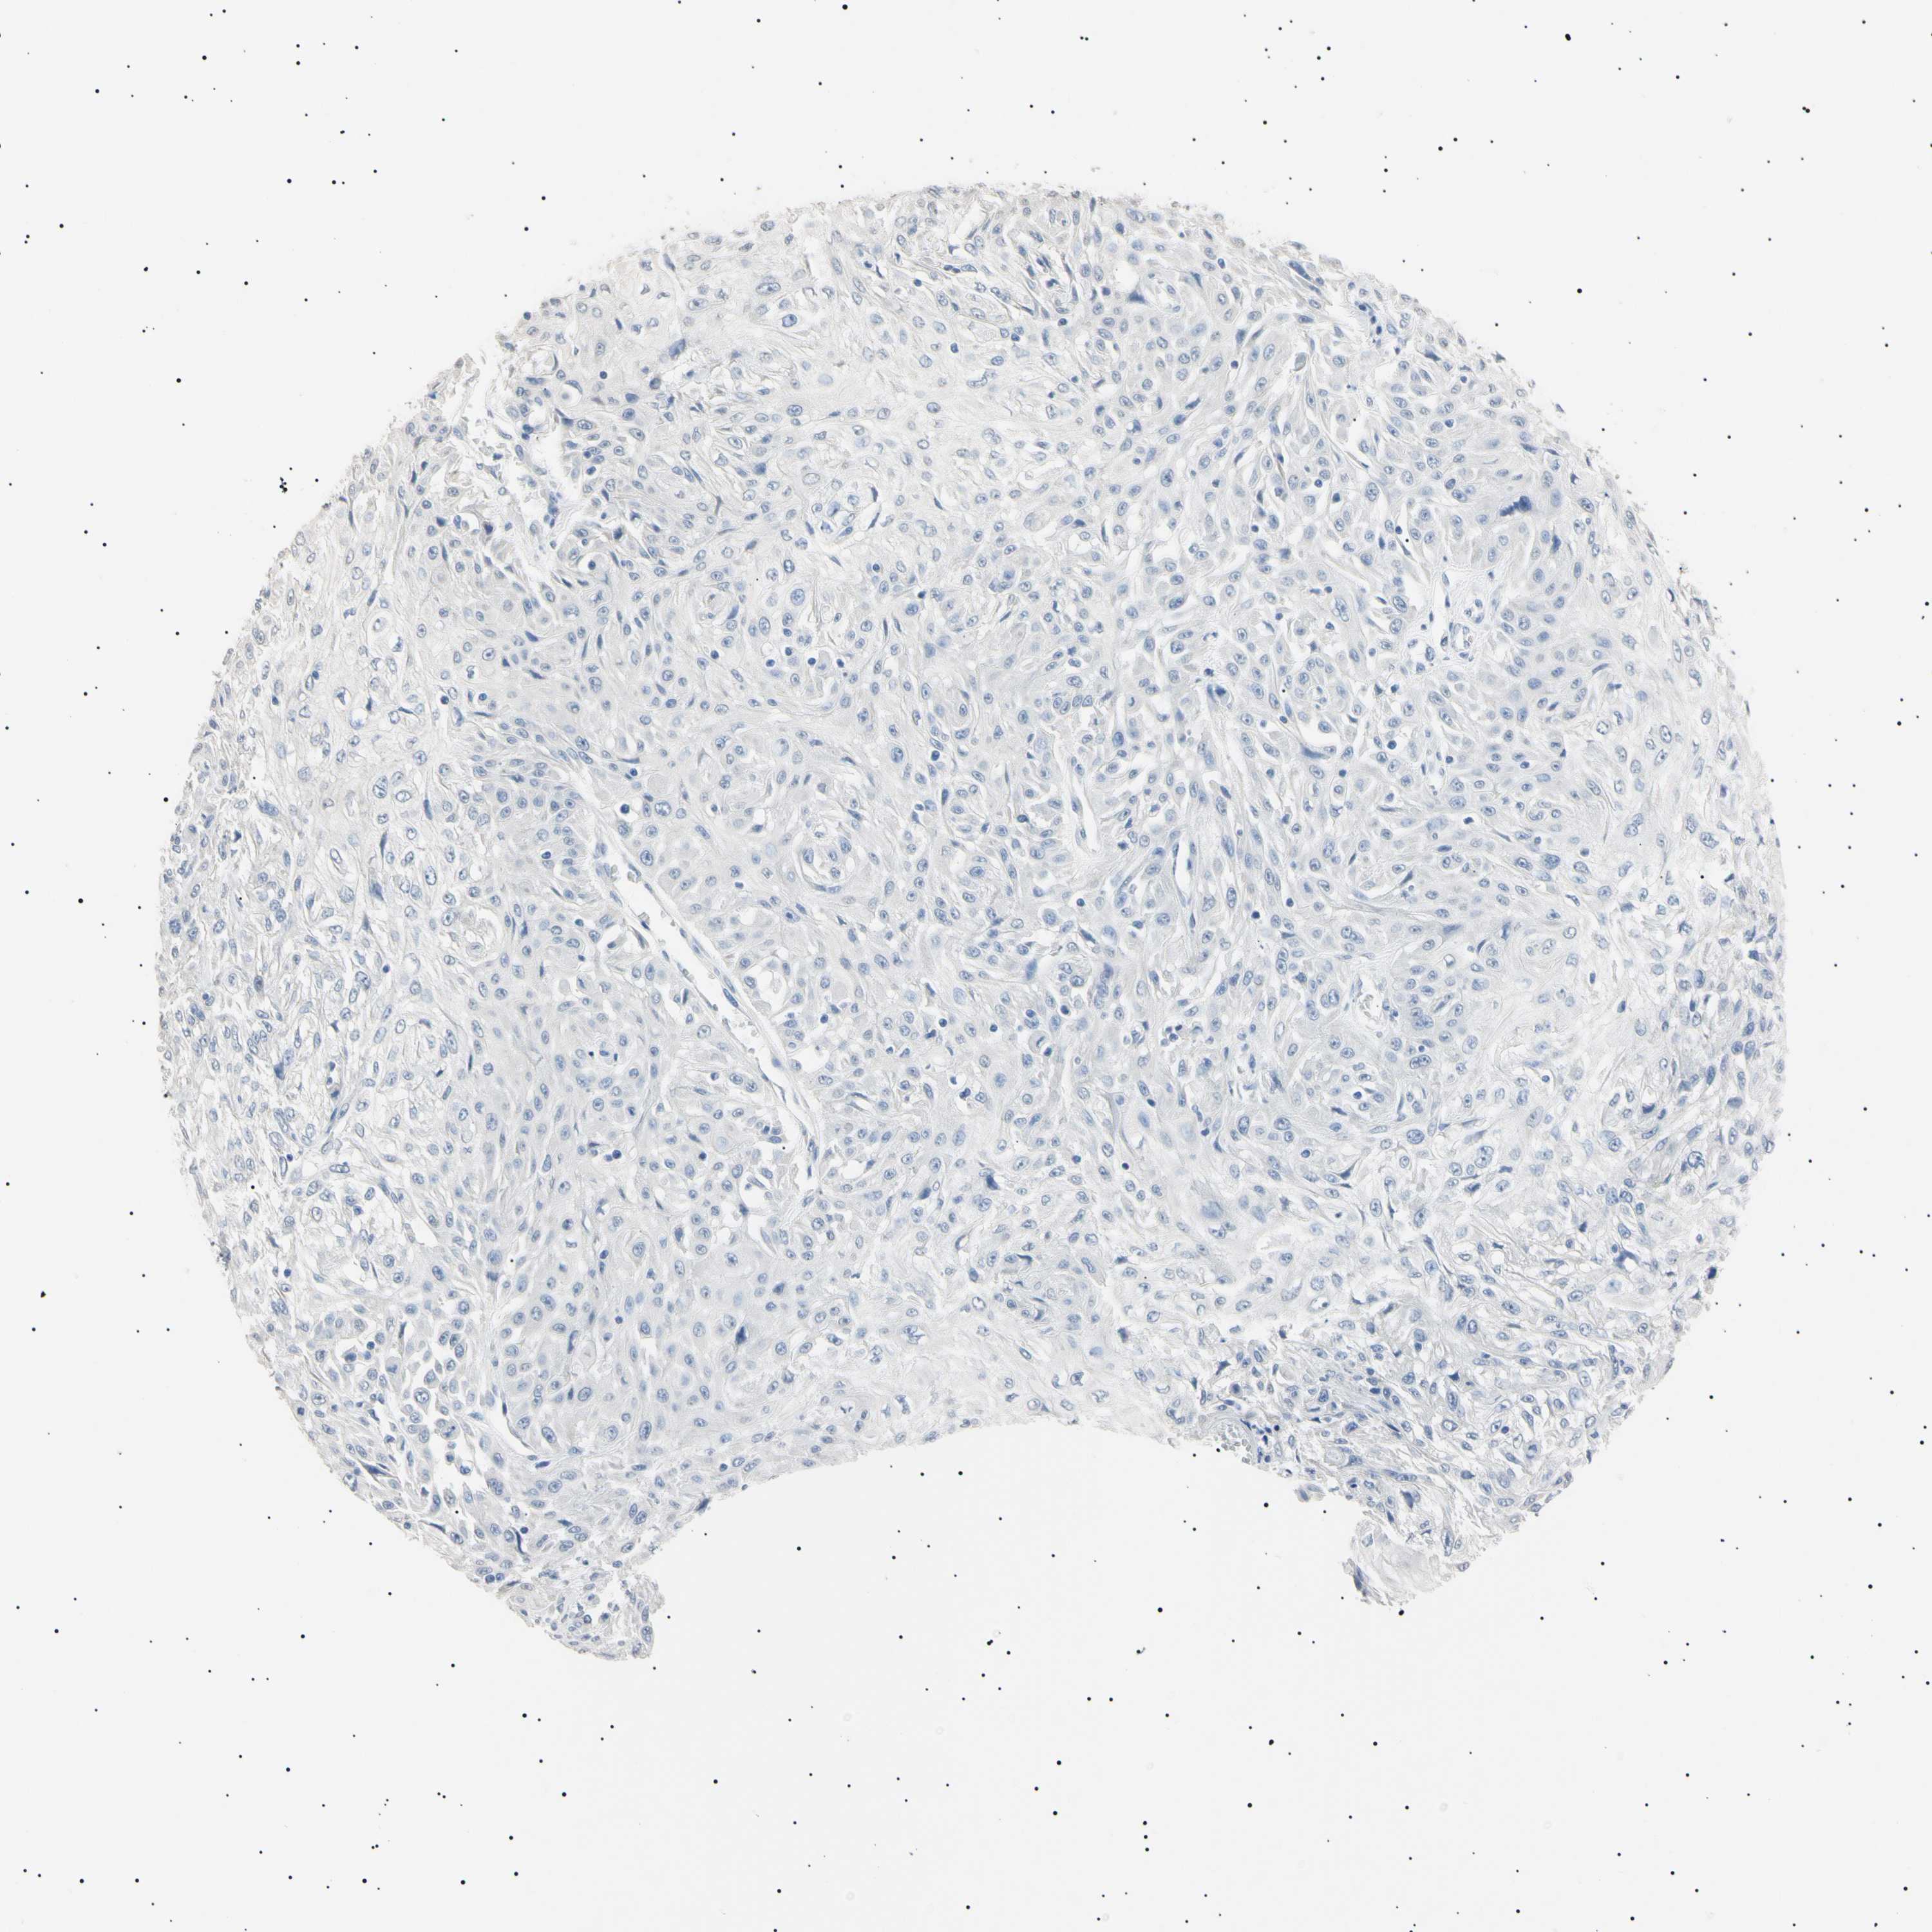

SKIN CANCER - Protein expressioni

A mouse-over function shows sample information and annotation data. Click on an image to view it in a full screen mode. Samples can be filtered based on level of antibody staining by selecting one or several of the following categories: high, medium, low and not detected. The assay and annotation is described here.

Antibody stainingi

Antibody staining in the annotated cell types in the current human tissue is reported as not detected, low, medium, or high, based on conventional immunohistochemistry profiling in selected tissues. This score is based on the combination of the staining intensity and fraction of stained cells.

Each image is clickable and will lead to virtual microscopy that enables deeper exploration of all samples and also displays staining intensity scores, fraction scores and subcellular localization as well as patient and tissue information for each sample.

Antibody CAB000042

Staining

High

Medium

Low

Not detected

Intensity

Strong

Moderate

Weak

Negative

Quantity

>75%

75%-25%

<25%

None

Location

Nuclear

Cytoplasmic/membranous

Cytoplasmic/membranous,nuclear

Basal cell carcinoma

Squamous cell carcinoma, NOS

Squamous cell carcinoma, metastatic, NOS